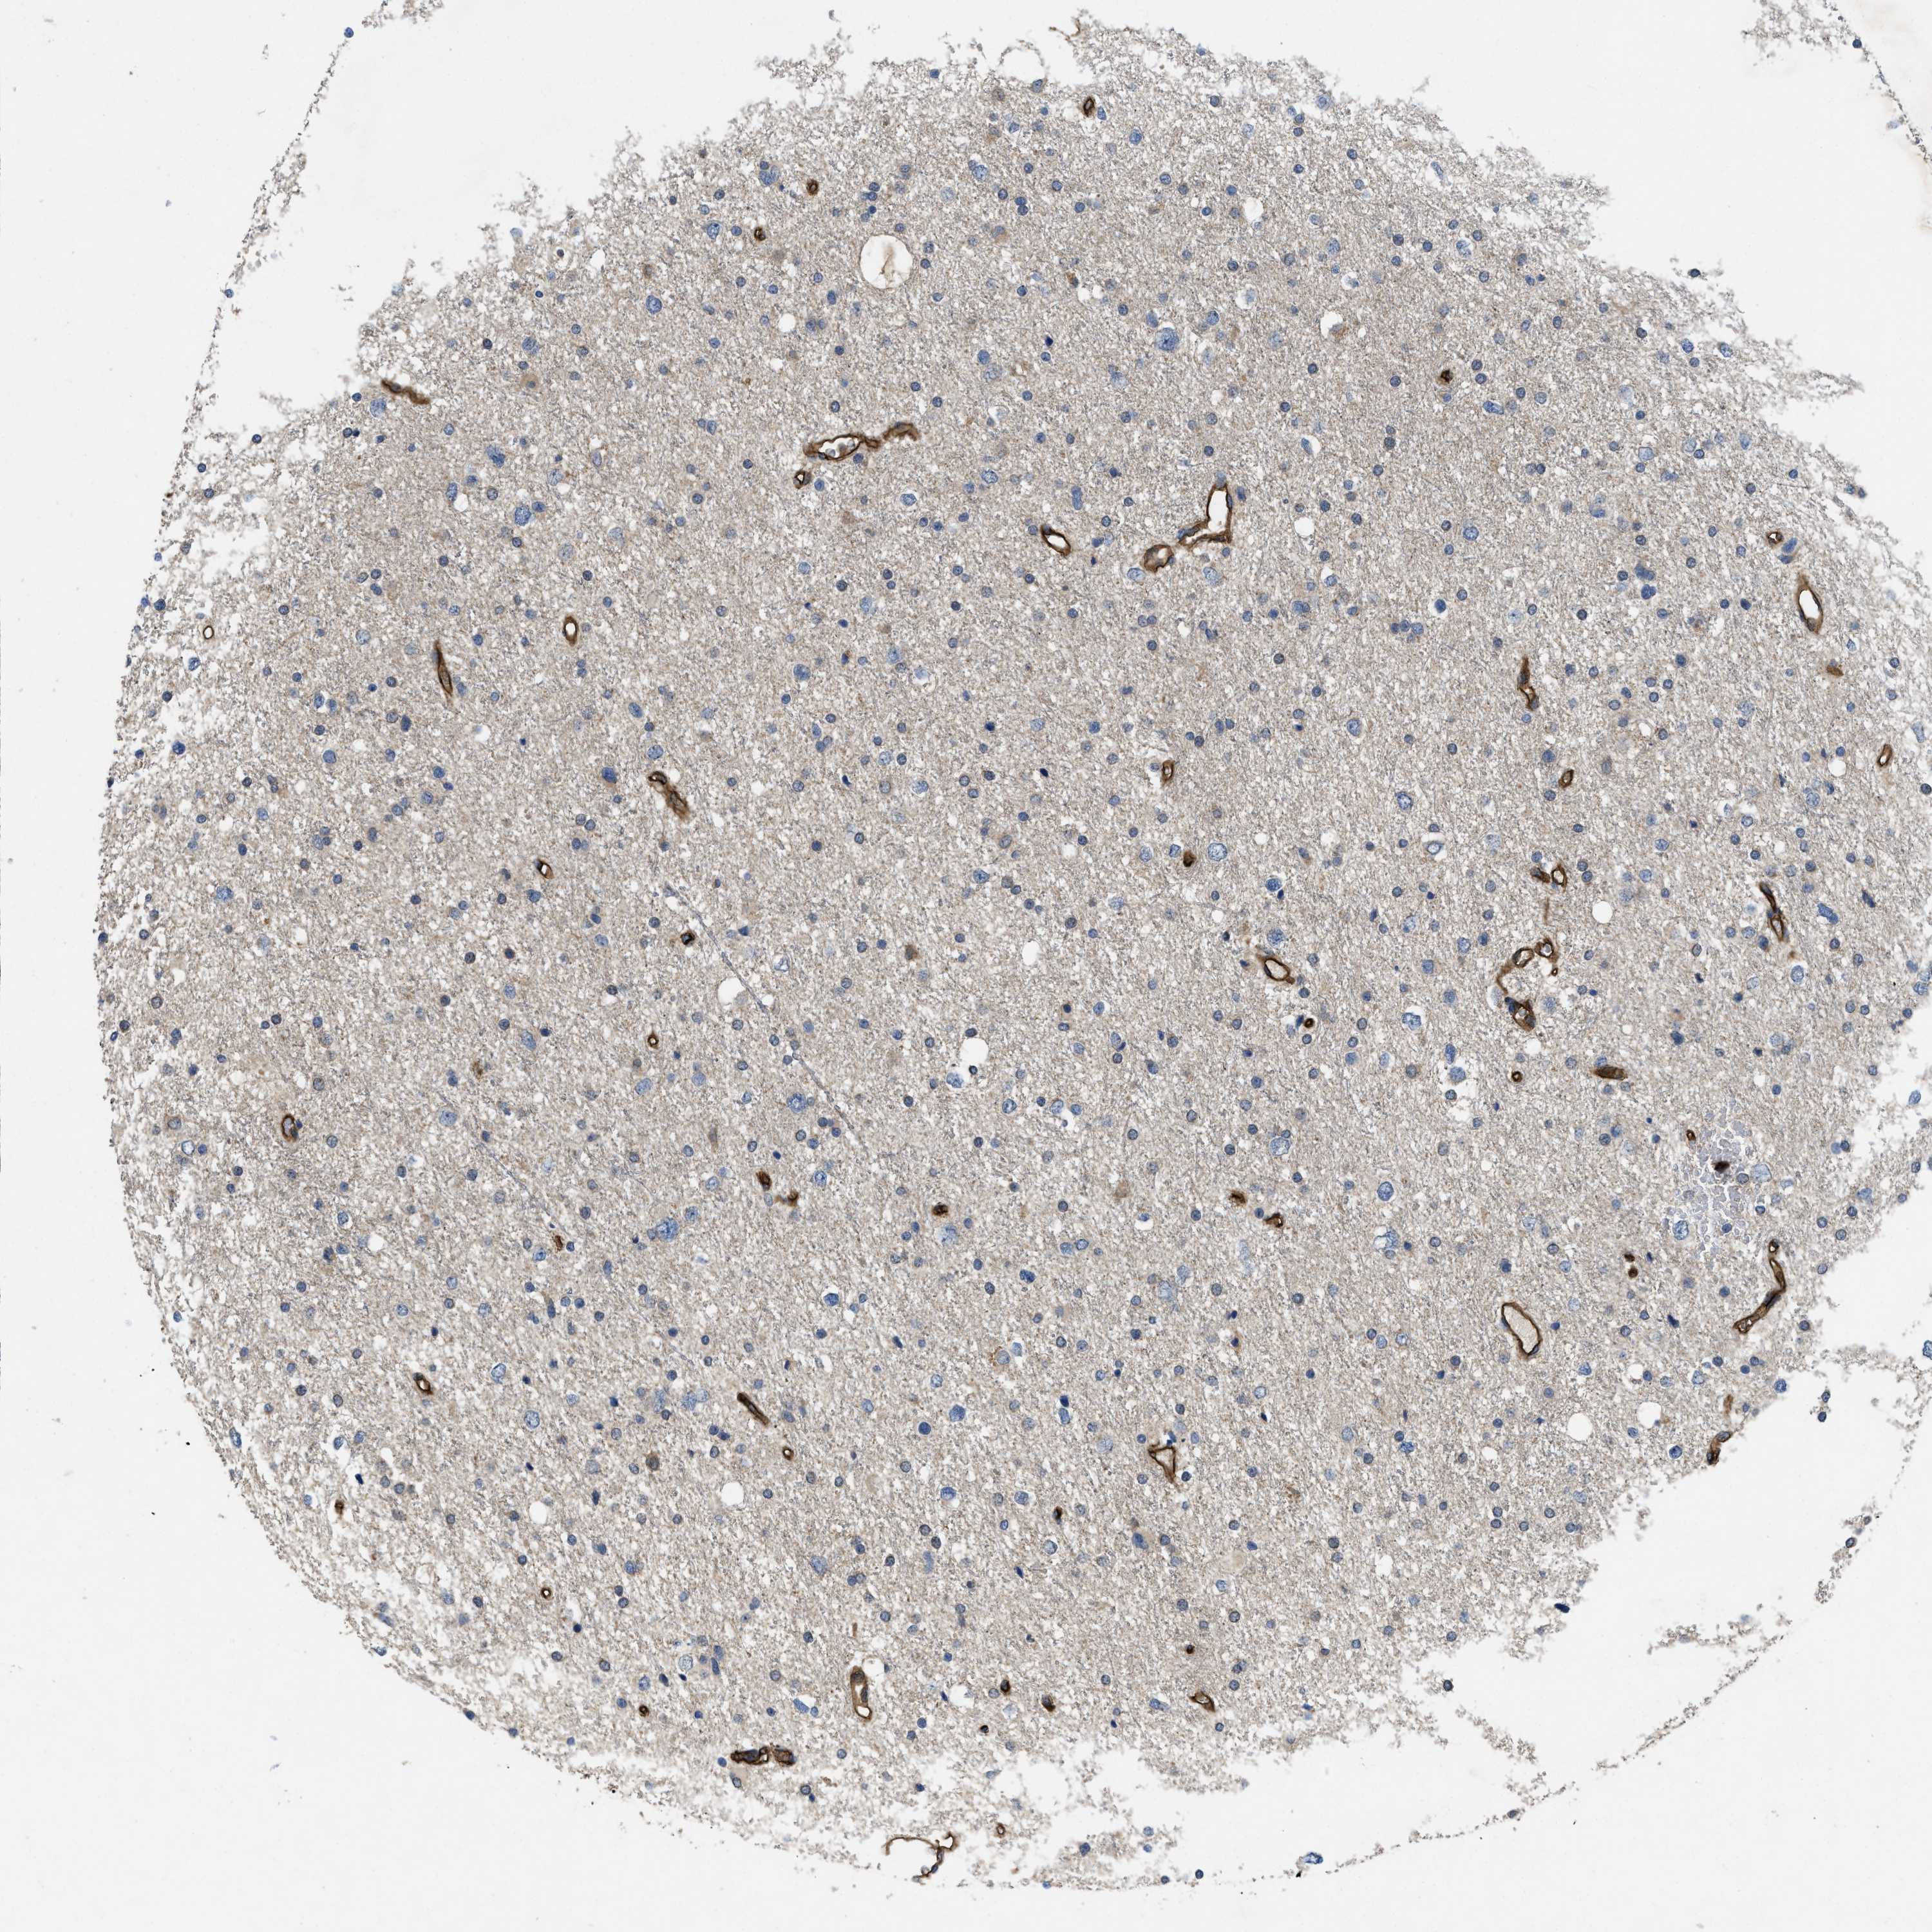

GLIOMA - Protein expressioni

A mouse-over function shows sample information and annotation data. Click on an image to view it in a full screen mode. Samples can be filtered based on level of antibody staining by selecting one or several of the following categories: high, medium, low and not detected. The assay and annotation is described here.

Note that samples used for immunohistochemistry by the Human Protein Atlas do not correspond to samples in the TCGA dataset.

Antibody stainingi

Antibody staining in the annotated cell types in the current human tissue is reported as not detected, low, medium, or high, based on conventional immunohistochemistry profiling in selected tissues. This score is based on the combination of the staining intensity and fraction of stained cells.

Each image is clickable and will lead to virtual microscopy that enables deeper exploration of all samples and also displays staining intensity scores, fraction scores and subcellular localization as well as patient and tissue information for each sample.

Antibody HPA013659

Antibody HPA015639

Glioma, malignant, High grade

Glioma, malignant, Low grade